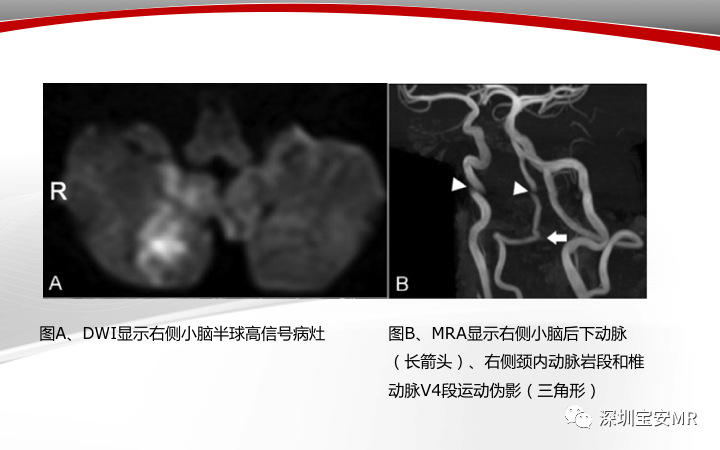

【病例】小脑后下动脉夹层1例MR